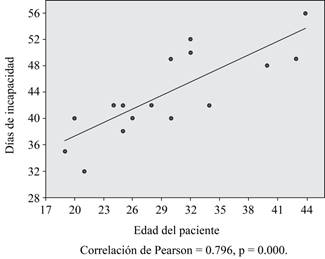

El tiempo medio de incapacidad otorgada a los pacientes fue 42.06 (de 28 a 56) ± 7.894 días.

La correlación entre la edad y los días de incapacidad otorgados fue estadísticamente significativa (p = 0.000) y se muestra en la Figura 4.